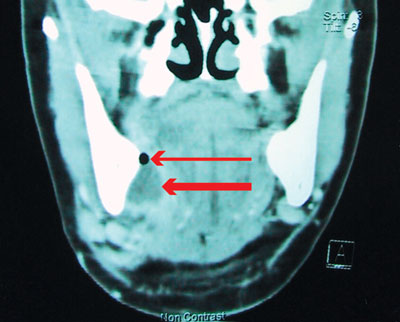

He was admitted for airway observation and given intravenous benzylpenicillin and metronidazole. The next day he was unable to completely open his mouth. After awake fibreoptic intubation, the two teeth were removed and the abscess drained. (The clinical and radiological findings for a patient with a similar diagnosis are shown in Box 1, B–D.)